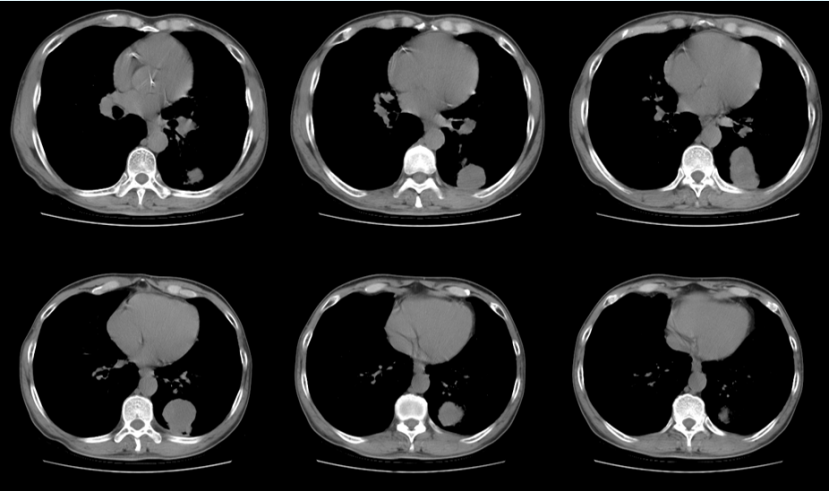

• 影像学:2月24日胸片提示右肺下叶病变,2月25日胸片可见病变范围迅速扩大(图3)

3  复查胸片对比